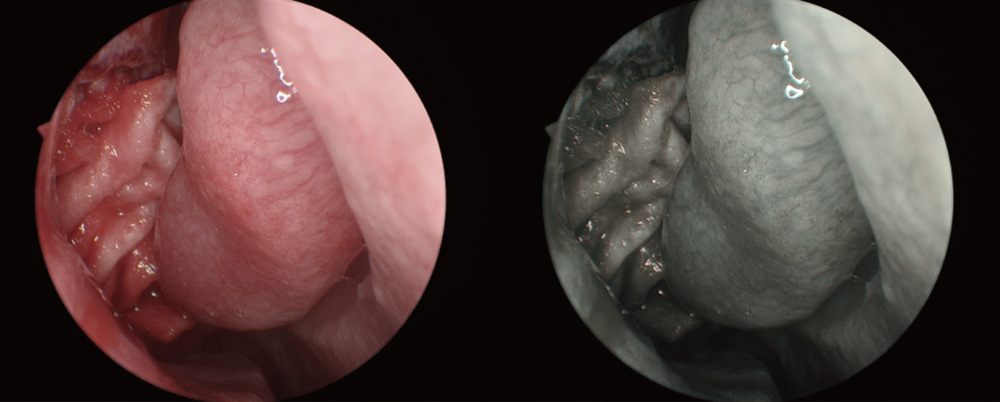

Automatic Scene Recognition, Intelligent Brightness Adjustment

Smart exposure: Determine different detection areas according to different scene and accurately match the exposure parameters without the need to manually switch department modes.

Small diameter scope scene (e.g. hysteroscope)

Laparoscope scene

Intelligent Image Algorithm, Even in Extreme Circumstances